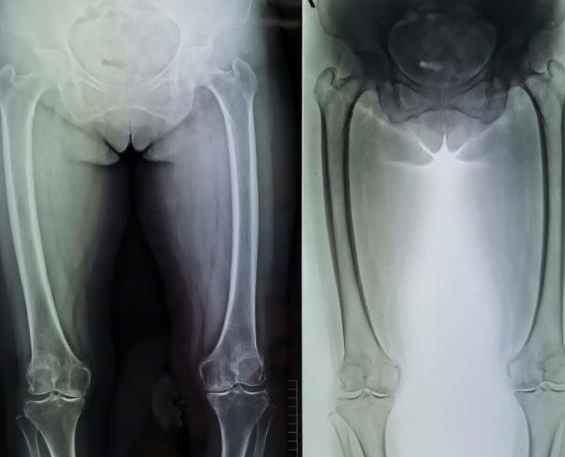

于阿姨变成了O型腿

近日,62岁的于阿姨就诊于包医一附院关节运动医学科。“膝关节疼痛已经七八年了,有时候吃点止疼药,但没啥改善。后来发展到走路时间稍微长点儿就疼痛加重,腿也慢慢变成了O型腿,连100米也走不到。”

随后,于阿姨入院包医一附院关节运动医学科,拍片子有很明显的膝关节内翻以及关节面磨损等。经诊断为双侧膝关节骨性关节炎。

于阿姨手术前后对比图

通过前期的系统治疗效果没有明显改善后,包医一附院关节运动医学科副主任医师刘鹤鸣决定为于阿姨进行人工关节置换手术。“因为考虑到于阿姨的年龄比较大,怕一次做两条腿她耐受不了,所以暂时先为她做了一条腿的膝关节置换。”